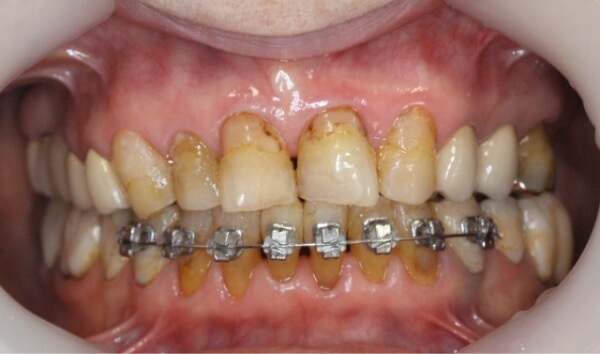

術前

上下の前歯に、大きな隙間があります。

歯は削らずにブラケットを使用して、上下の前歯6本の隙間を閉じる治療を始めることになりました。